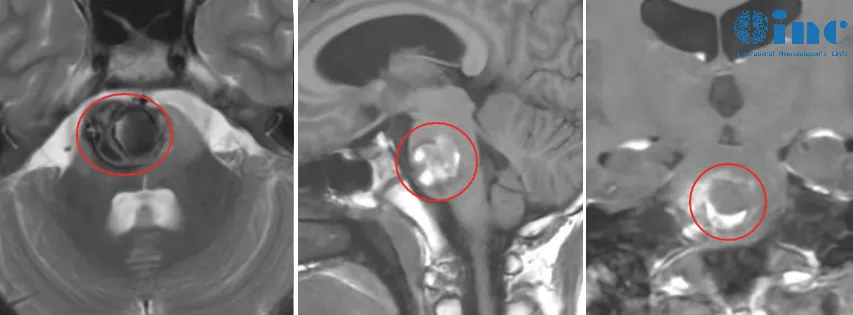

术前影像

检查结果如同一记重锤,沉重打击了这个家庭:诊断为脑干海绵状血管瘤,且病灶位置极为凶险,位于脑干桥脑区域。医生神情凝重地给出建议:采取保守观察策略,定期进行复查。